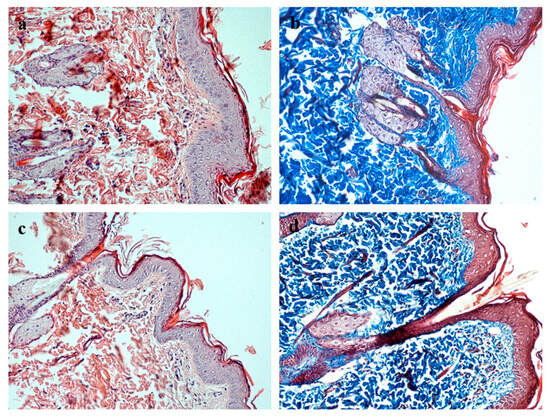

Histological examination of the healed full-thickness skin defects in the experimental group revealed the complete restoration of all morphological skin layers (Figure 6). A well-organized, multilayered epithelium formed over the wound site, with clearly delineated basal, spinous, granular, and cornified layers comparable in thickness and architecture to those of intact skin. The underlying connective tissue comprised mature, fibrous dermis containing sebaceous glands and hair follicles. Collagen fibers stained by Masson’s trichrome displayed dense packing and orientation characteristic of normal dermis. No signs of chronic inflammation or fibrotic remodeling were detected in the regenerating tissue. The newly formed skin integrated seamlessly with the surrounding intact tissue, with no distinct boundary between the repair zone and adjacent skin.

Figure 6. Comparative histological analysis of the healed skin area in the experimental group and intact rat skin. Magnification ×200. (a,b) Healed skin defect on day 15 in the experimental group: stained with hematoxylin and eosin (a) and Masson’s trichrome (b); (c,d) intact skin stained with hematoxylin and eosin (c) and Masson’s trichrome (d).